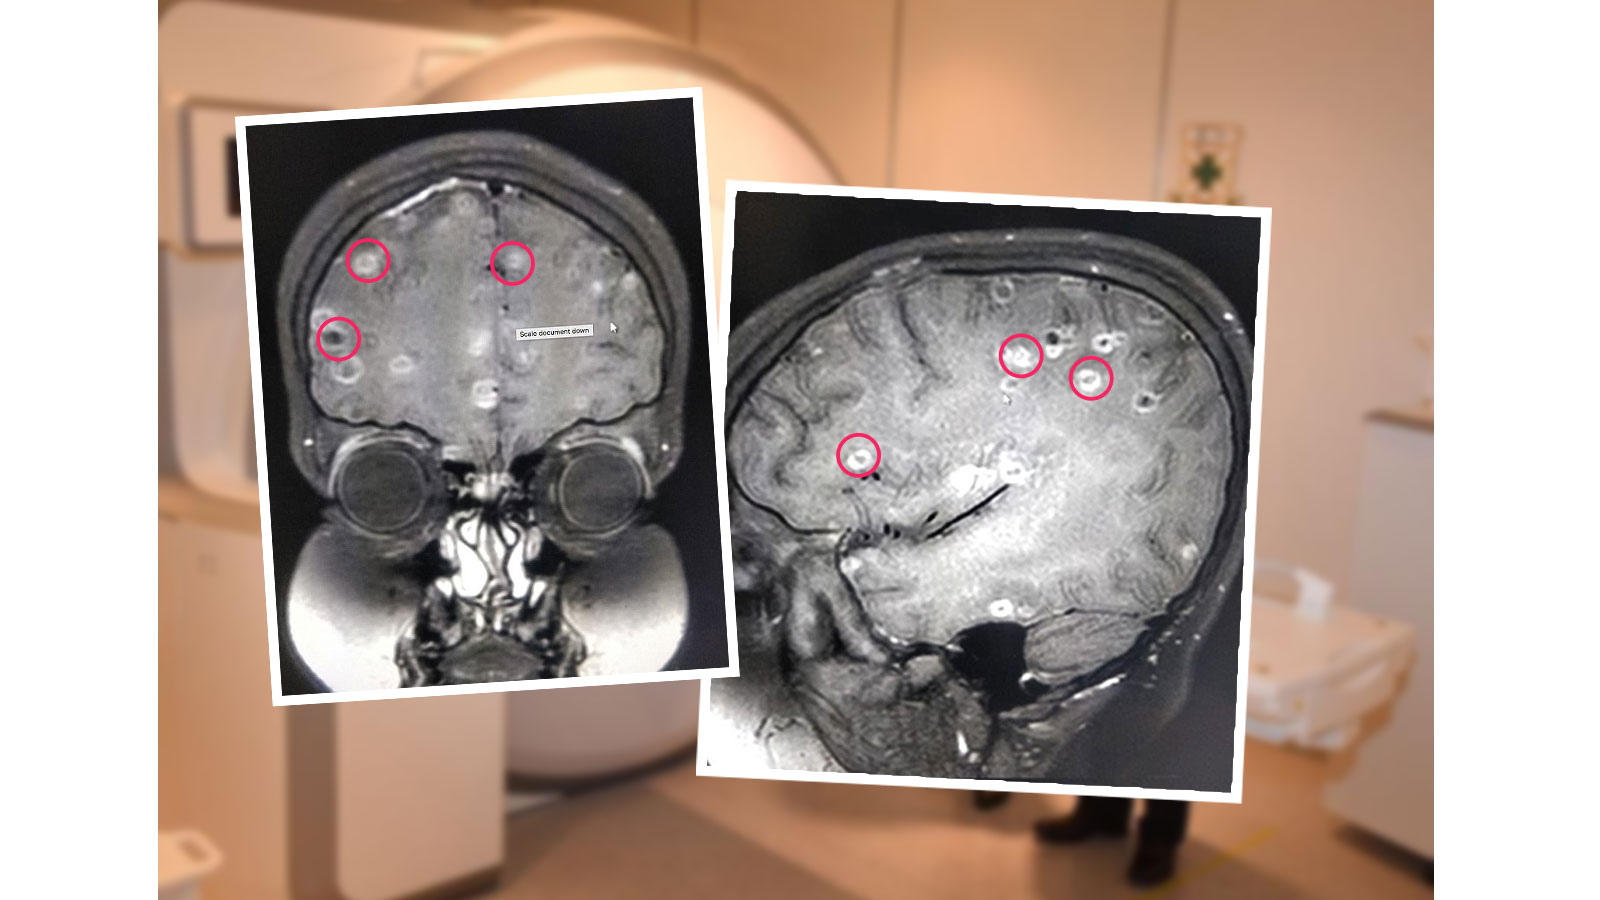

脑囊虫病影像学表现

本期寄生虫的包囊膜完整,宿主免疫反应轻微.在此分期,包囊中只有液体.